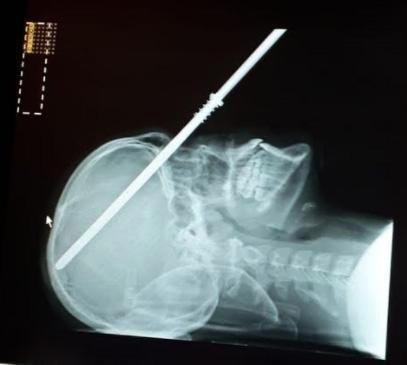

Devon White 14 tuổi, đến từ Chelmsford, Essex đã bị thanh lao đâm xuyên qua mắt trong khi đi nghỉ ở Ý cùng gia đình. Cảnh sát cho biết cây súng phóng lao sắc nhọn đã bị hỏng chốt và không được khóa đúng cách nên khi White đứng lên, ngọn lao bắn luôn vào đầu cậu bé.

Đây là một cuộc phẫu thuật rất hiếm và không phổ biến. Tôi từng xử lý vết thương do dao đâm, nổ súng, tai nạn xe hơi nhưng chưa bao giờ thực hiện cho một cậu bé 14 tuổi với một thanh thép cắm sâu 30 cm trong đầu mình. Cậu bé đã quá may mắn vì thanh thép đi qua khoang sau của mắt, xuyên qua xương đỉnh. Đó là phần trên của hộp sọ và bảo vệ bộ não”, bác sĩ chủ trì ca phẫu thuật Alberto Delitala, 66 tuổi chia sẻ.

Bác sĩ cũng cho biết phần tinh vi nhất của ca phẫu thuật là loại bỏ thanh thép một cách hoàn toàn mà không gây thêm bất cứ thiệt hại nào cho não bộ. Trước khi tiến hành phẫu thuật, đội cứu hộ cũng đã cắt bớt một nửa thanh thép đi.